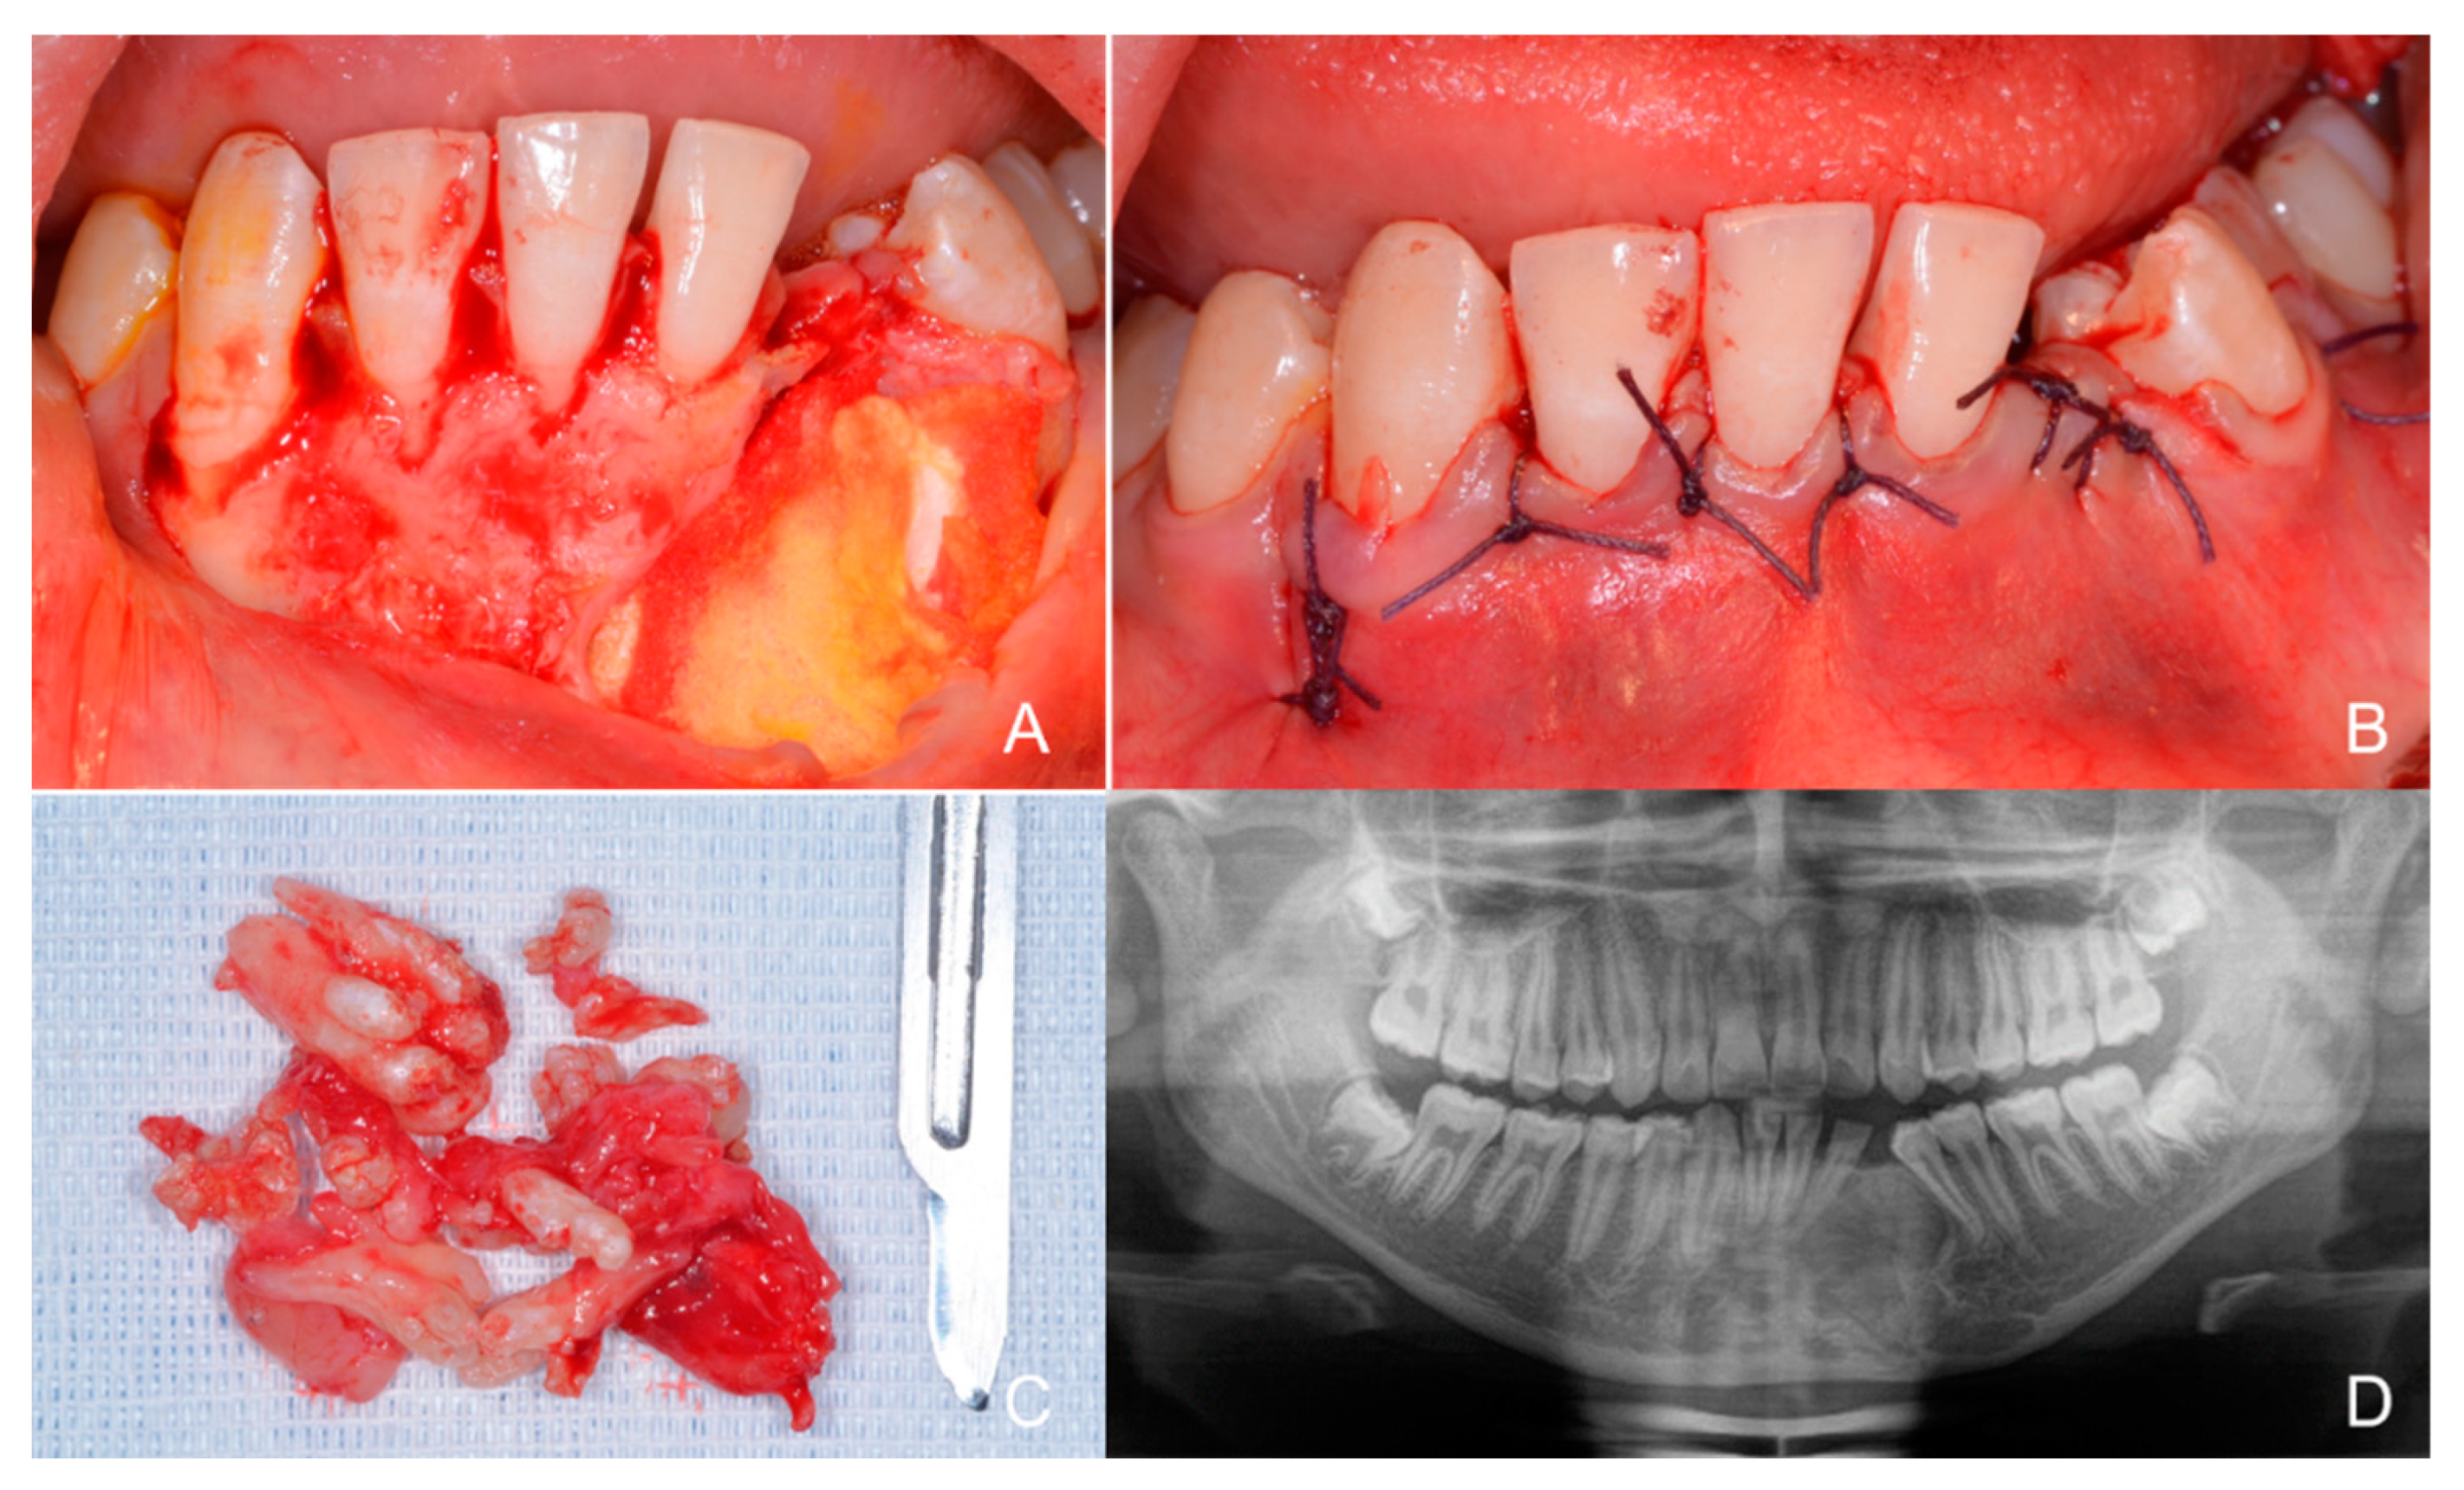

1.1. Case Number 1

1.2. Case Number 2

1.3. Case Number 3